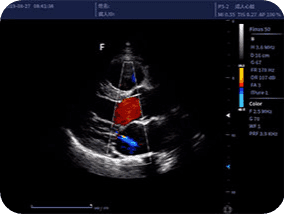

Клінічна Галерея